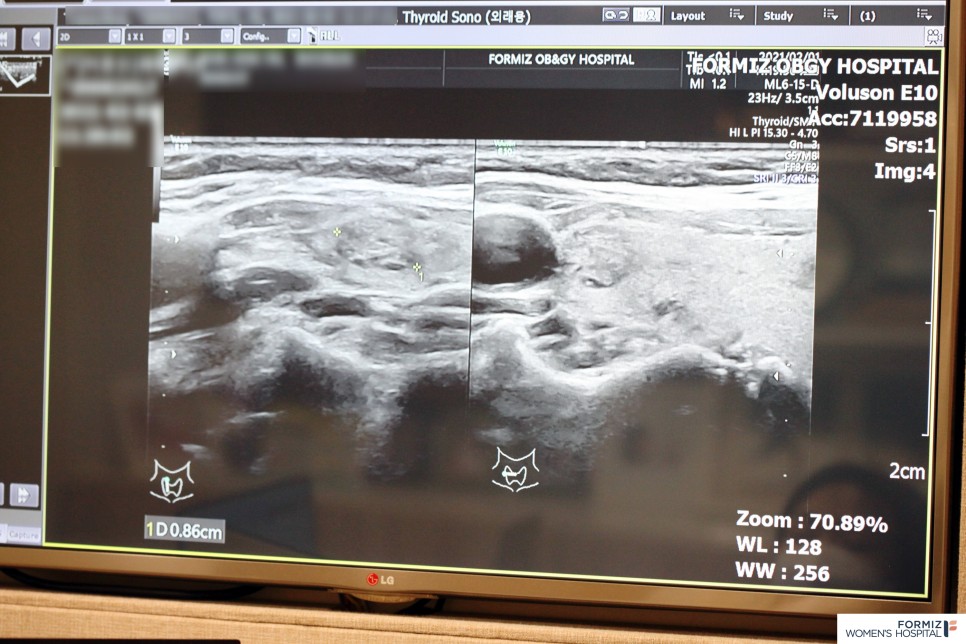

미세침 흡입 검사에서 갑상선 결절 여부 확인 갑상선 결절은 손으로 만지고 확인할 수 있는 경우는 소수에 불과하며 대부분 갑상선 검사를 통해 발견하는 것이 판별에 정확합니다. 갑상선 검사는 크게 4가지로 구분됩니다. 먼저 #갑상선 초음파 검사는 형태와 크기, 결절의 성장과정 등을 살펴볼 수 있으며, 만약 그 형태가 악성으로 의심될 경우 조직검사를 통해 자세한 조사를 실시합니다. 이때 주로 사용되는 것이 미세침 흡입 검사로 갑상선 결절의 악성 여부를 확인할 수 있습니다. 미세한 바늘을 삽입해 결절 세포를 채취한 뒤 굵고 긴 바늘을 이용해 갑상선 조직을 채취하는 방식으로 진행돼 진단 정확성이 매우 높습니다. 혈액검사에서는 혈액을 채취하여 갑상선의 기능 이상, 자가면역, 재발 여부를 판단할 수 있습니다. 컴퓨터 단층촬영인 시티촬영은 악성암으로 판별된 뒤 진행하는 정밀검사로 갑상선암이 주위 조직으로 퍼진 정도와 림프절 전이 여부를 파악할 수 있습니다.

갑상선 초음파 검사 결과에 따라 치료방법 결정 #갑상선 초음파 검사 후 암이 아닌 양성의 경우 불편함이 없으면 치료하지 않아도 됩니다. 하지만 부풀어 일상생활에 지장을 줄 정도로 불편하다면 고주파 치료나 알코올 경화로 피부 절개 없이 치료가 가능합니다. 고주파 치료는 세계적으로 많이 이용하는 방법으로 고주파열을 이용하여 결절을 태워 버리는 방법입니다. 비수술적 방법으로 절개할 필요가 없으며 흉터가 생기지 않아 부담이 없습니다. 결절 부위만 정확히 치료하기 때문에 주변 부위에 영향을 주지 않고 갑상선에 영향을 주지 않으면서 기능이 살아있어 만족도가 높은 시술입니다.

만약 결과가 악성암이라면 수술을 통해 빨리 치료를 받으시기 바랍니다. 포미즈 여성 병원에서는 정확한 갑상선 초음파 검사를 받을 수 있습니다. 저희 병원의 갑상선 초음파 검사는 원스톱으로 진단하고 있으며, 일부 대학병원에서 실시할 수 없는 총조직검사를 25년 이상 시행하고 있어 전문적이고 신속한 검사가 가능합니다. 모든 질환이 그렇듯 갑상선도 예방과 관리가 중요합니다. 따라서 정기적인 갑상선 검사를 통해 미리 건강을 지켜 주시기 바랍니다.